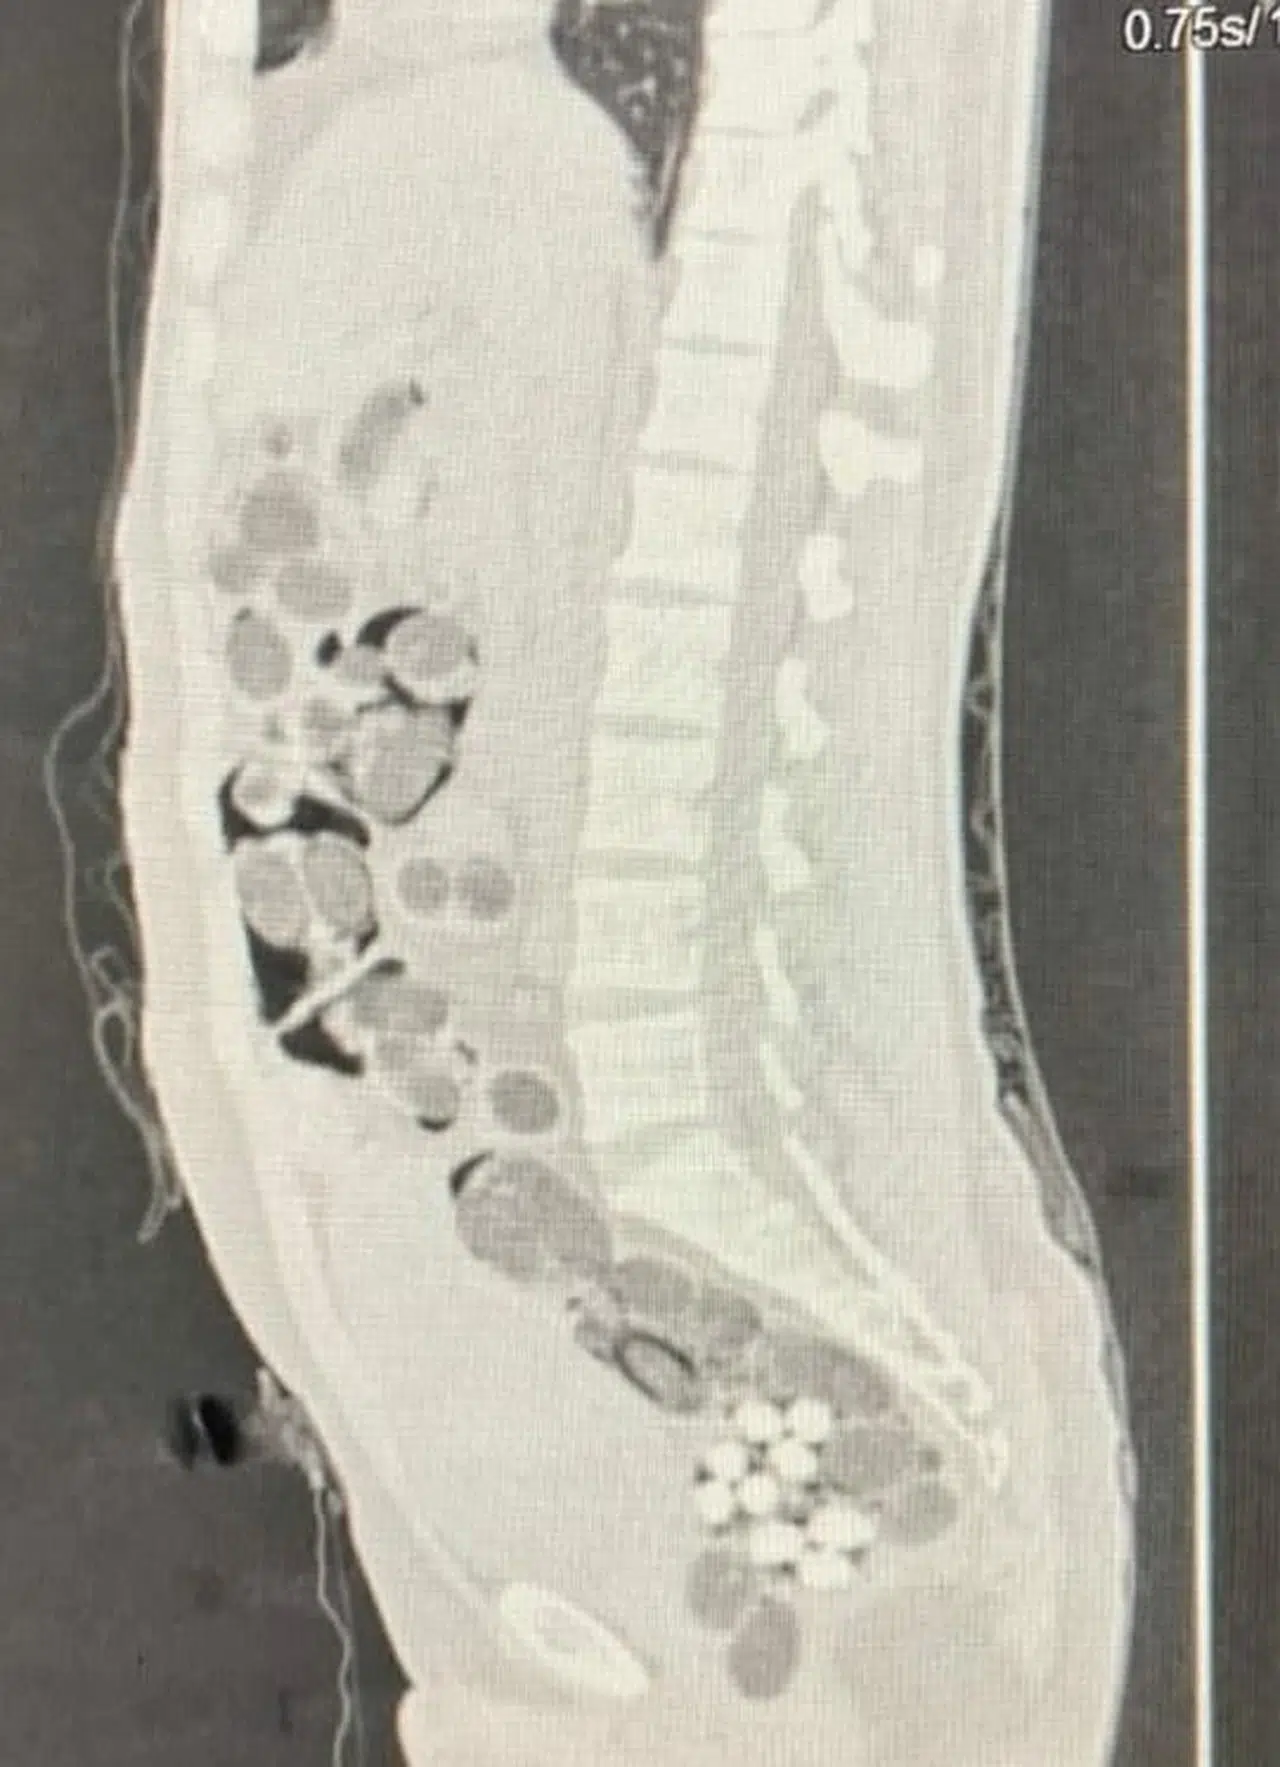

Ramazan ÇETİN/DENİZLİ, (DHA)-DENİZLİ'de uçakla seyahat eden yabancı uyruklu yolcunun midesinden 219 paket halinde 1 kilo 144 gram skunk, 178 gram metamfetamin, 90 uyuşturucu hap ve 7 gram Afyon sakızı çıktı. Şüpheli ile alıcı, operasyonla yakalanıp, tutuklandı.

Denizli İl Emniyet Müdürlüğü Narkotik Suçlarla Mücadele Şube Müdürlüğü ekipleri, 2 Şubat'ta Çardak Havalimanı'na inen yabancı uyruklu kişinin uyuşturucu taşıdığını belirledi. Takibe alınan şüpheli, uyuşturucu maddeyi teslim edeceği yabancı uyruklu alıcı ile buluştuğu sırada operasyonla yakalandı. Şüpheli ile alıcı, gözaltına alındı. Denizli Devlet Hastanesi'ne götürülüp, röntgeni çekilen yabancı uyruklu şüphelinin midesinden 219 paket halinde 1 kilo 144 gram skunk, 178 gram metamfetamin, 90 uyuşturucu hap ve 7 gram Afyon sakızı çıktı. Paketteki uyuşturucular doğal yollarla çıkartılırken, 2 şüpheli işlemlerinin ardından tutuklandı. (DHA)